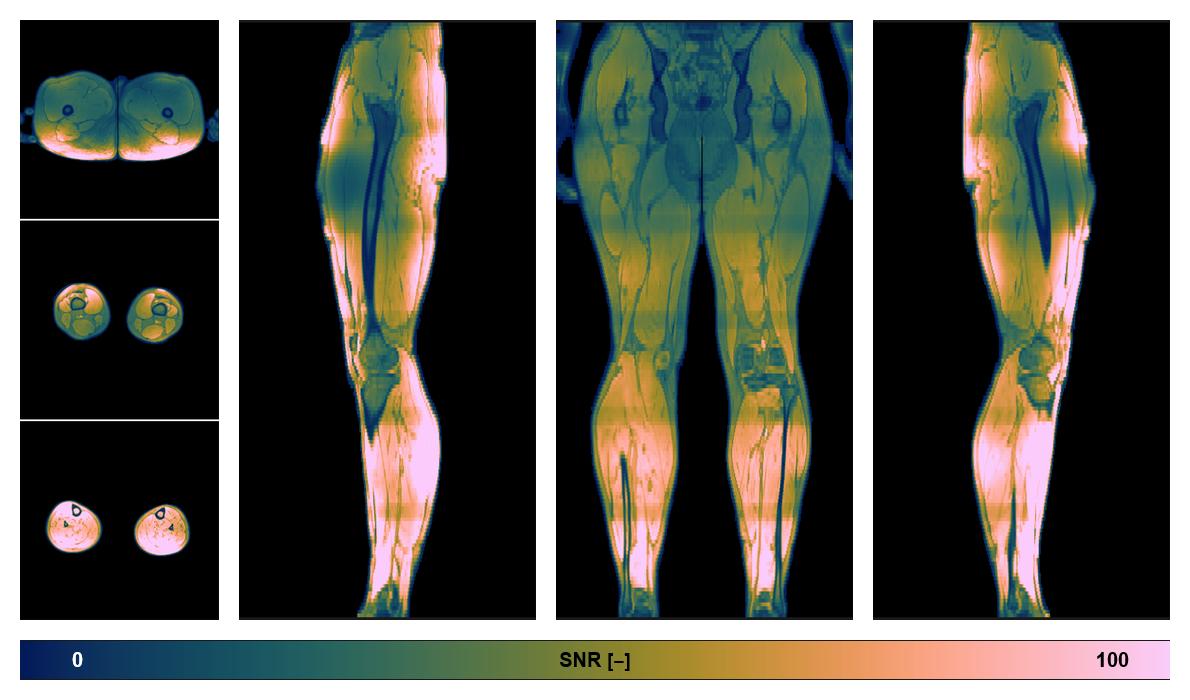

• SNR of the unweighted image

SNR distribution of the unweighted diffusion data.